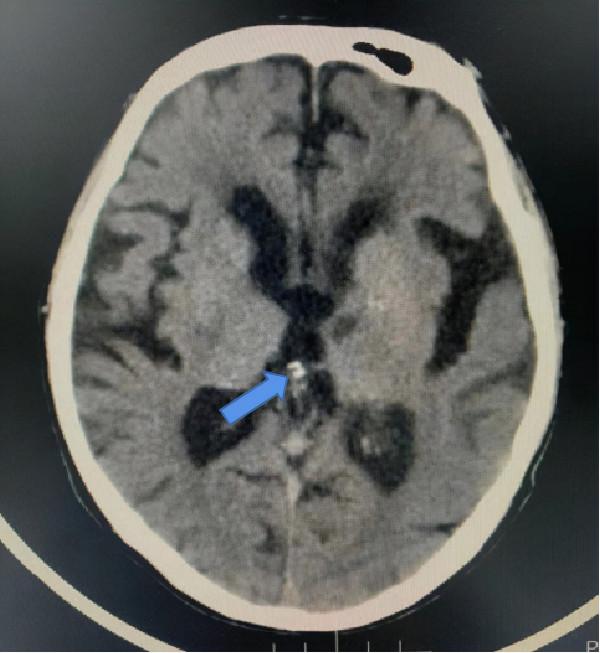

腦,松果體鈣化(箭頭所指,白色,結節狀)。病例同時存在腦白質脫髓鞘,腦萎縮,腔梗。

各種單發鈣化灶(如肺內鈣化灶)。鈣化分為生理性和病理性鈣化,通俗地講,人體的某些部分就喜歡鈣鹽沉積,如顱內的松果體,這就是生理性的。

病理性的鈣化,多種多樣,可以是壞死的組織,如結核病,也可以是鈣鱗代謝障礙的疾病等。比如肺內 鈣化灶,其實就是可能過去得過肺炎或肺結核後鈣鹽沉積在壞死組織裡的結果,完全不用管。